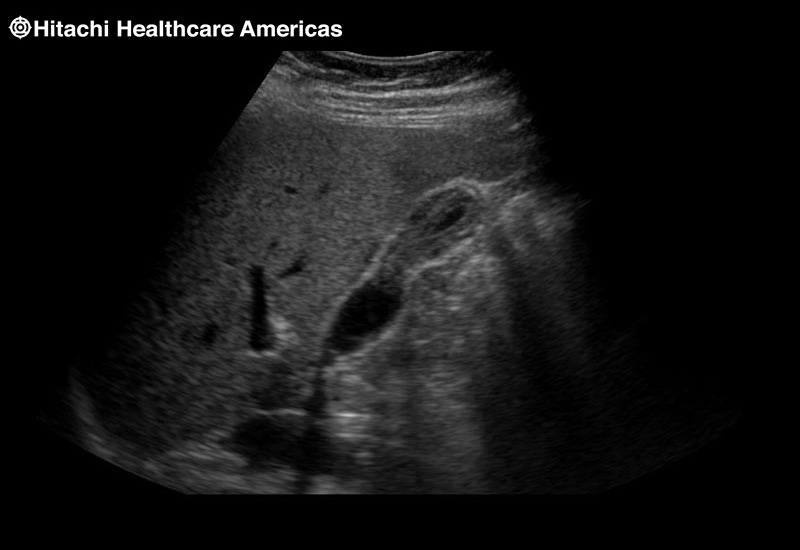

Learn moreArietta 65

The Arietta 65 has many advanced and unique probes that fully cover the expanding range of procedures that benefit from ultrasound guidance.

Learn moreArietta 65

The Arietta 65 has many advanced and unique probes that fully cover the expanding range of procedures that benefit from ultrasound guidance.

Our smallest footprint allows for enhanced contact in tight spaces

Our newest probe, the L51K allows the surgeon access to difficult-to-reach areas that no other probe on the market can go. The unique design and proximal location of the attaching mechanism provides full wrist articulation and easier grasp and release.